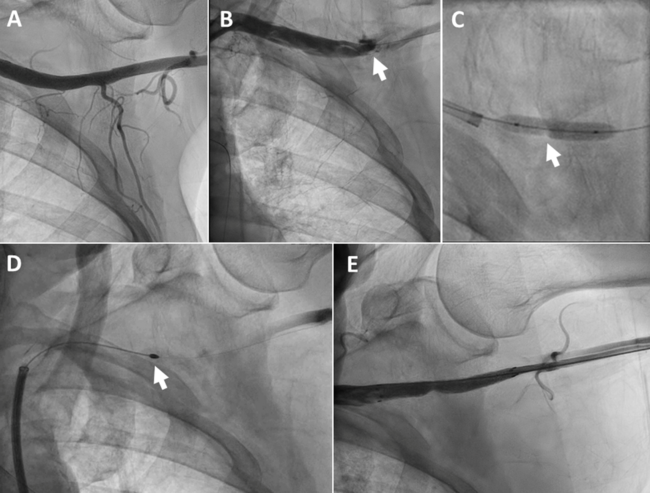

An 84-year-old woman with severe symptomatic AS, renal failure, and recent left-main coronary stenting was referred for TAVR. A 14-Fr sheath was used for the procedure. The access site in the left femoral artery was sealed using a Perclose ProStyle VCD. Angiography revealed critical stenosis at the access site, which could not be dilated with a balloon (Figure 2, Video 4). Rotational atherectomy via transbrachial access using a 2.0-mm burr ablated the occlusive sutures (Video 5) and enabled implantation of a 6 x 40-mm Fluency stent graft (Video 6).